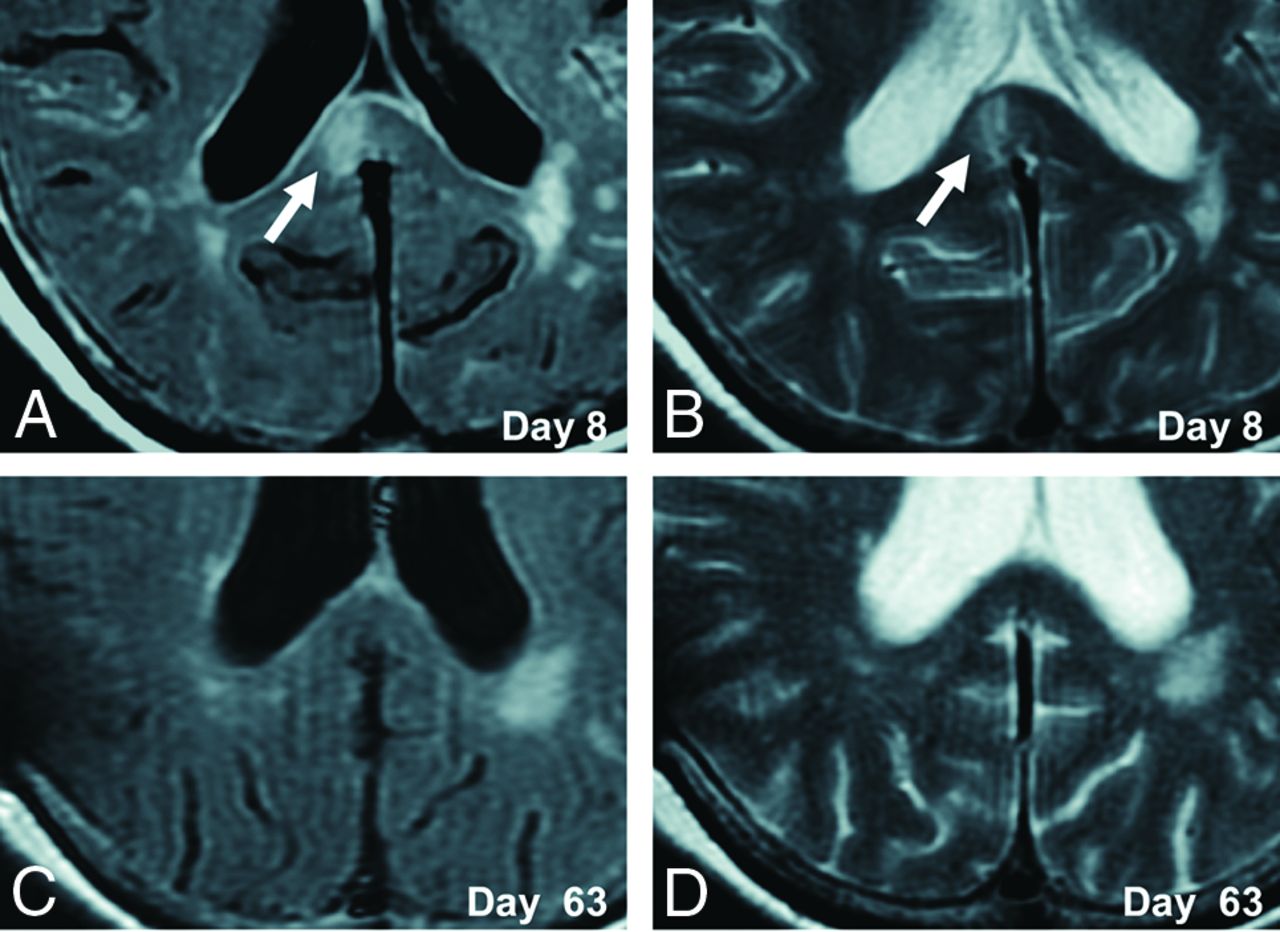

A 70-year-old woman presented with poor-grade SAH (Hunt and Hess grade 4). CT revealed Fisher group 3 SAH, and MRA demonstrated a 5-mm-diameter aneurysm on the anterior communicating artery. The patient underwent aneurysm coiling on day 2. This patient developed DCI and received regional arterial infusion of fasudil hydrochloride hydrate 3 times. She also developed hydrocephalus and underwent ventriculoperitoneal shunting. The patient had mild disorientation and was discharged home with an mRS score of 3. Although no abnormality was evident on DWI in this patient on admission (Fig 2A), a high-signal area appeared in the splenium of the corpus callosum on SAH day 7 (Fig 2B). The lesion gradually faded and had completely resolved by day 63 (Fig 2C–F). This change was thought to represent CLOCC and was also observable on FLAIR and T2WI (Fig 3).

Serial DWI in an illustrative case. A 70-year-old woman presented with poor-grade SAH due to rupture of an aneurysm (diameter, 5 mm) at the anterior communicating artery. DWI on admission shows no lesion (A). CLOCC appear on days 7–8 (B and C) and gradually resolve (D–F).

Serial FLAIR and T2WI in an illustrative case. CLOCC (white arrows) are observed in the splenium on FLAIR and T2WI on day 8 (A and B) and resolve by day 63 (C and D).